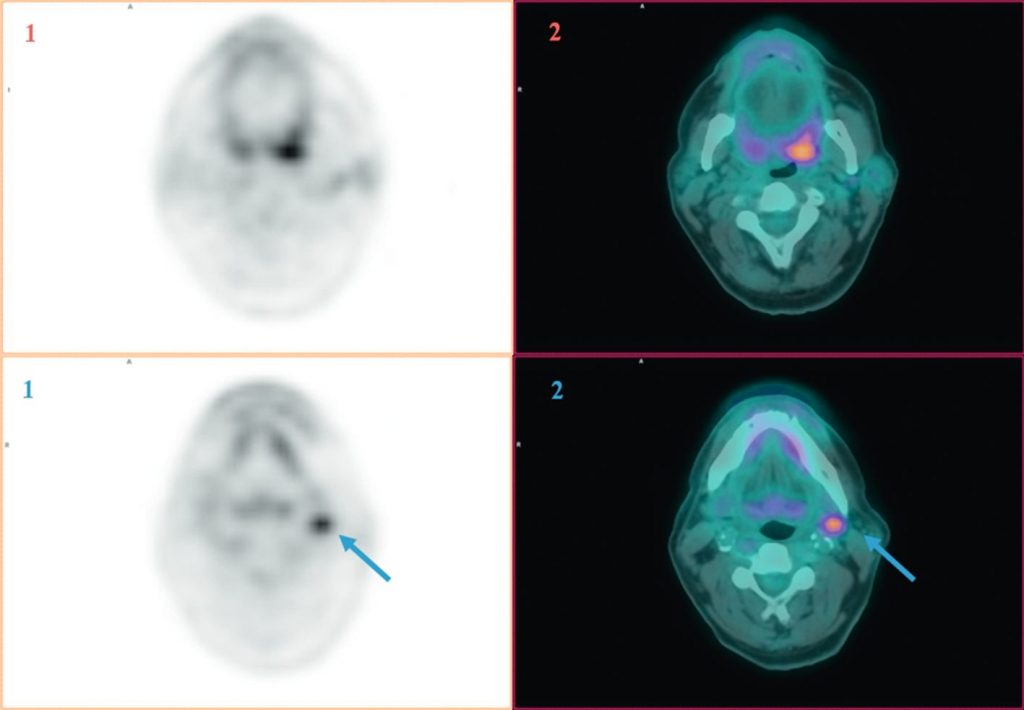

Une TEP-TDM au 18FDG est réalisée en première intention et recommandée pour la recherche de localisation de la tumeur primitive en cas d’adénopathie métastatique cervicale sans cancer primitif connu — lésion primitive retrouvée dans 30 à 50 % des cas.

La TEP-TDM au 18FDG est réalisée de préférence avant la réalisation des biopsies pharyngées compte tenu des risques de faux positifs induits par les remaniements inflammatoires. Elle permet de guider les biopsies (figure 63.1).

Fig. 63.1 Images TEP au 18FDG (1) et TEP au 18FDG fusionnée à la TDM (2) en coupes axiales montrant une asymétrie de fixation en regard de l’oropharynx dans un contexte d’adénopathie métastatique sous-digastrique gauche sans porte d’entrée (flèche bleue) ayant permis de révéler un carcinome épidermoïde de l’amygdale gauche après biopsie ciblée.

Source : CERF, CNEBMN, 2022.